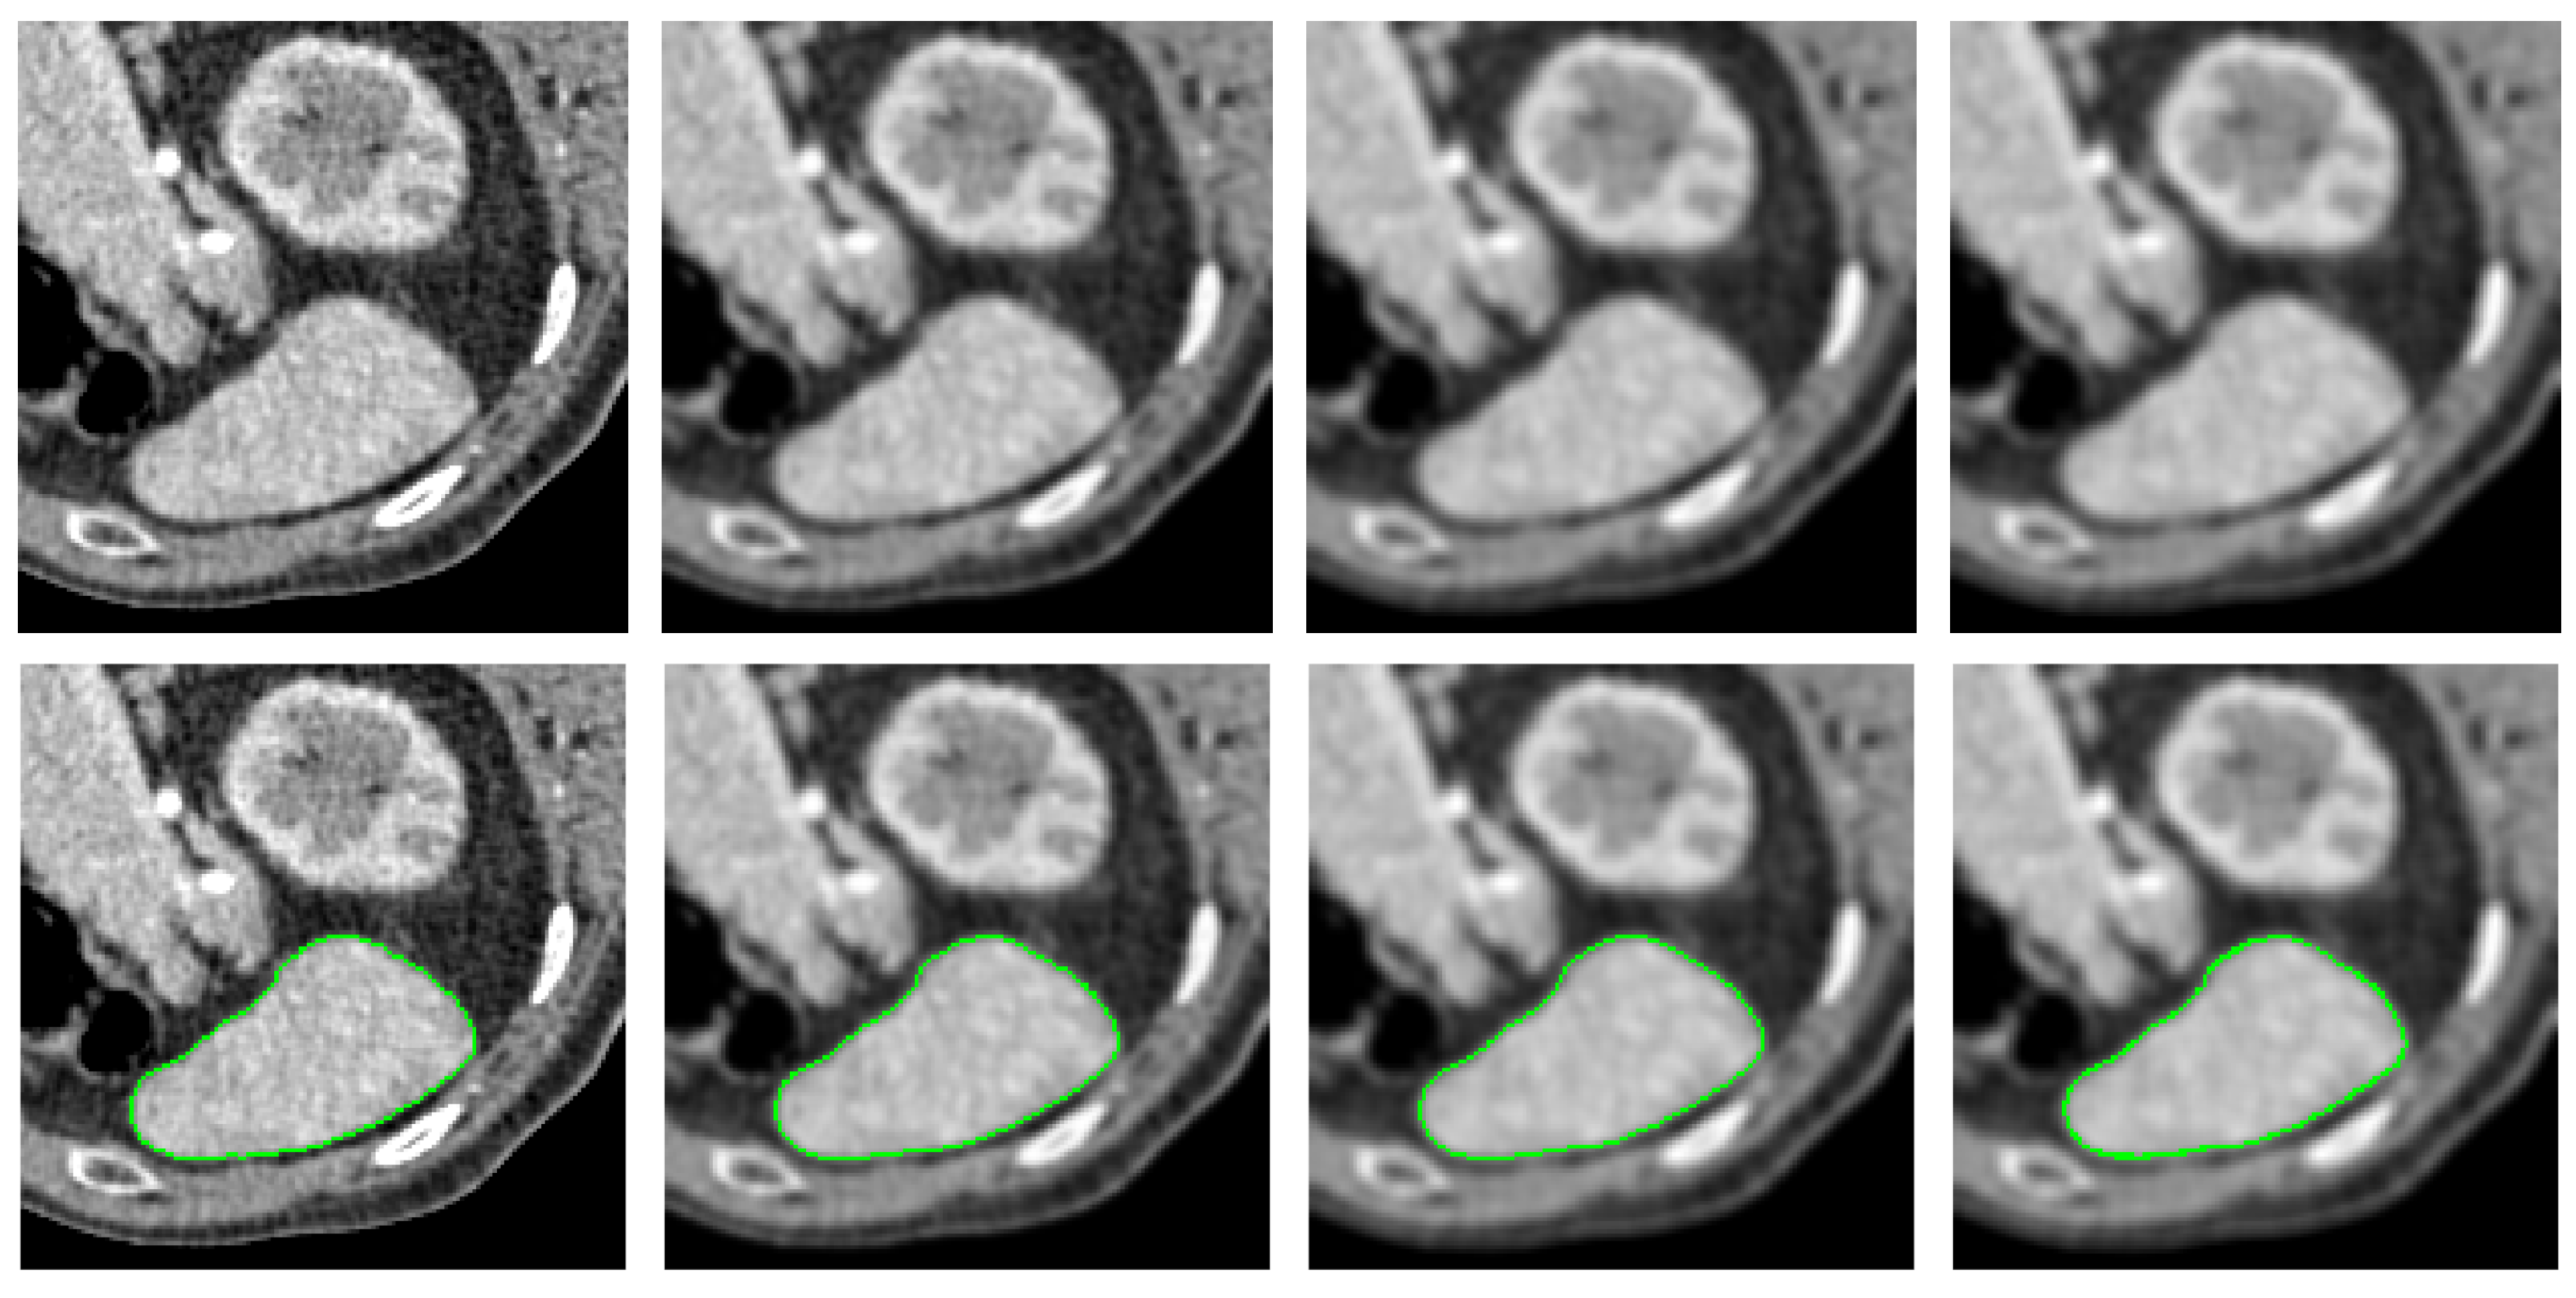

4.2. Qualitative Comparison Analysis

- Medical Images: For medical images, we select X-ray computed tomography (CT) scans from [41]. This dataset is commonly used in medical image segmentation evaluations, with image resolution ranging from to pixels, depending on the specific context of each test.

- The PolarMask model does not incorporate contour regularization. In scenarios where image quality is low or distorted by noise, such as in medical CT images, the absence of regularization can lead to unexpected and irregular segmentation results, highlighting significant room for improvement.